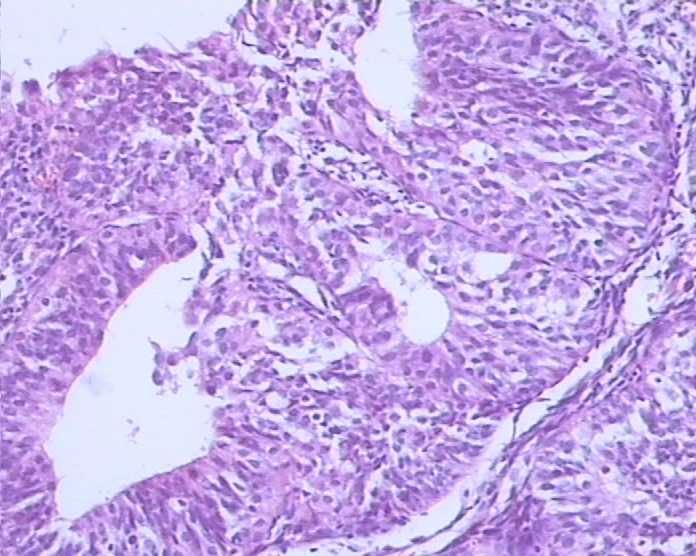

患者,女,30岁,阴道流血量多8天,伴血块;B超示内膜增厚。送检灰白灰红碎组织一堆,合计大小1cmx1cmx0.5cm。

复杂性增生伴重度非典型性。发展为癌的可能性较大,年龄较轻,治疗后复查,仍然如此,可以考虑手术。